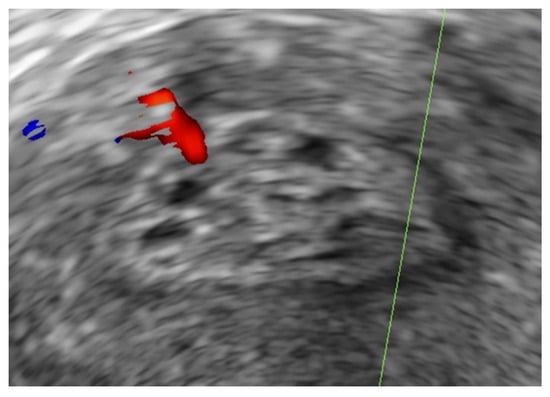

- Timmerman, D.; Verguts, J.; Konstantinovic, M.L.; Moerman, P.; Van Schoubroeck, D.; Deprest, J.; Van Huffel, S. The pedicle artery sign based on sonography with color Doppler imaging can replace second-stage tests in women with abnormal vaginal bleeding. Ultrasound Obstet. Gynecol. 2003, 22, 166–171. [Google Scholar] [CrossRef]

| Presence of a pedicle vessel b | 92 (41.4) | 12 (66.7) | n/a | 0.048 d |